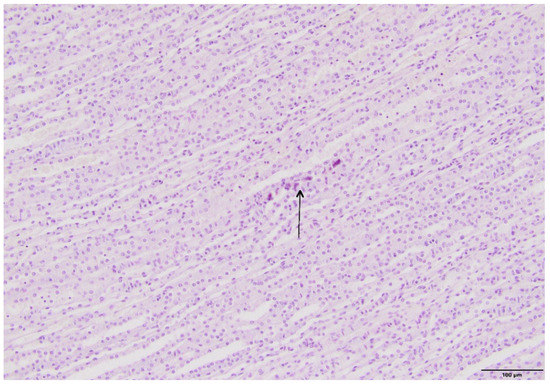

2.4. Kidney Histopathology